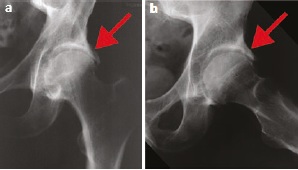

Schweregradeinteilung nach radiologischen Kriterien

Die Einteilung der Coxarthrose in verschiedene Schweregrade hilft bei der Therapieplanung und Prognoseeinschätzung. Dabei ist wichtig zu verstehen, dass die radiologischen Befunde nicht immer mit der Intensität der Beschwerden korrelieren.

| Grad 1 | Leichte Gelenkspaltverengung, erste Osteophyten | Meist asymptomatisch oder minimale Beschwerden | Konservative Therapie, Prävention, Bewegungstraining |

| Grad 2 | Mäßige Gelenkspaltverengung, deutliche Osteophyten | Belastungsschmerzen, leichte Steifigkeit | Physiotherapie, Medikation |

| Grad 3 | Deutliche Gelenkspaltverengung, subchondrale Sklerosierung | Ruhe- und Belastungsschmerzen | zunächst intensive konservative Therapie |

| Grad 4 | Gelenkspaltaufhebung, ausgedehnte Veränderungen | Schwere Funktionseinschränkung | Operative Therapie erwägen |